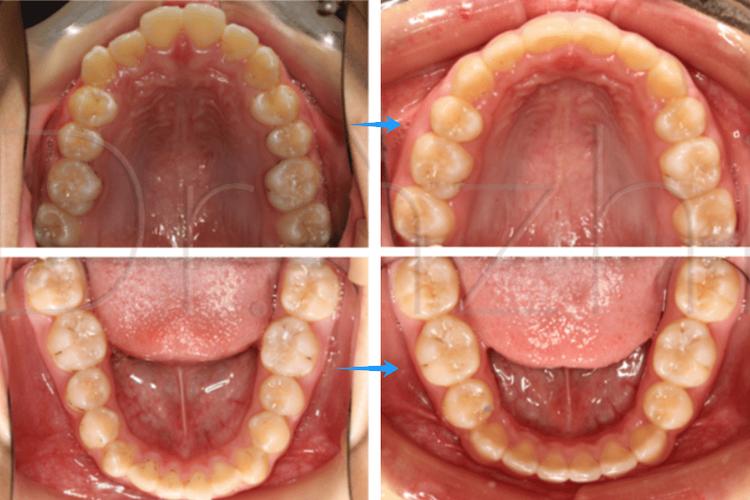

正畸拔牙是临床中常见的治疗手段,主要用于解决牙齿拥挤、前突、咬合关系异常等问题,而拔牙后的间隙管理是决定治疗效果的核心环节,间隙变化图作为记录和分析拔牙后牙齿移动轨迹、牙槽骨改建过程及最终效果的重要工具,通过动态影像和示意图直观展示了从间隙形成到关闭的全过程,为医生制定方案、监控治疗进度提供了科学依据,也让患者更清晰地理解治疗逻辑。

正畸拔牙通常选择第一前磨牙(上下颌各拔1-2颗),因其位置适中,既能提供足够间隙,又对邻牙功能影响较小,拔牙后,即刻形成的间隙大小约等于拔牙牙冠的近远中径(一般第一前磨牙牙冠宽度为5.5-7.0mm,平均约6.0mm),间隙两侧的牙齿(前牙和后牙)会因失去支撑而出现轻微倾斜:前牙可能向唇侧轻微移位,后牙向近中倾斜,但整体移动幅度较小(1mm),拔牙窝内充满血凝块,随后开始机化、骨改建,间隙变化图的初始阶段会清晰标注拔牙位置、间隙初始宽度,以及邻牙的初始倾斜角度,为后续移动设定基准。

随着血凝块机化成肉芽组织,拔牙窝开始初步愈合,牙槽骨破骨细胞在压力侧吸收骨组织,成骨细胞在张力侧增生,邻牙在咀嚼力及矫治器轻力作用下开始向间隙移动:前牙向远中(拔牙侧)移动,后牙向近中移动,但速度较慢(每月约0.5-1.0mm),间隙变化图中可见:拔牙窝密度逐渐增高,邻牙牙体开始倾斜,间隙宽度较初始缩小约10%-20%。

主动间隙关闭阶段(3-12个月,核心阶段)

此阶段通过矫治器(如滑动法关闭曲、种植支抗等)施加持续、轻柔的生物力,推动牙齿快速移动,前牙(切牙、尖牙)整体向远中移动,后牙(磨牙)向近中移动,同时保持垂直高度稳定,间隙变化图特征显著:前牙切端逐渐向拔牙侧移动,后牙近中面与对颌牙建立初步接触,间隙宽度每月缩小约1.0-1.5mm;牙槽骨改建活跃,压力侧可见骨吸收透射影,张力侧骨密度增高;牙根位置随牙齿移动调整,逐渐趋于平行。

当间隙基本关闭后,进入细节优化阶段,医生通过调整弓丝转矩、更换细丝(如0.018英寸不锈钢丝)进行“轻力细调”,纠正牙齿的轻微扭转、转矩异常,建立稳定的咬合关系(如尖牙引导、组牙功能颌),间隙变化图显示:牙齿排列整齐,牙根平行,牙槽骨改建完成,密度均匀;牙龈形态逐渐恢复,若存在牙龈凹陷,可能需通过牙周手术或正畸牵引改善。